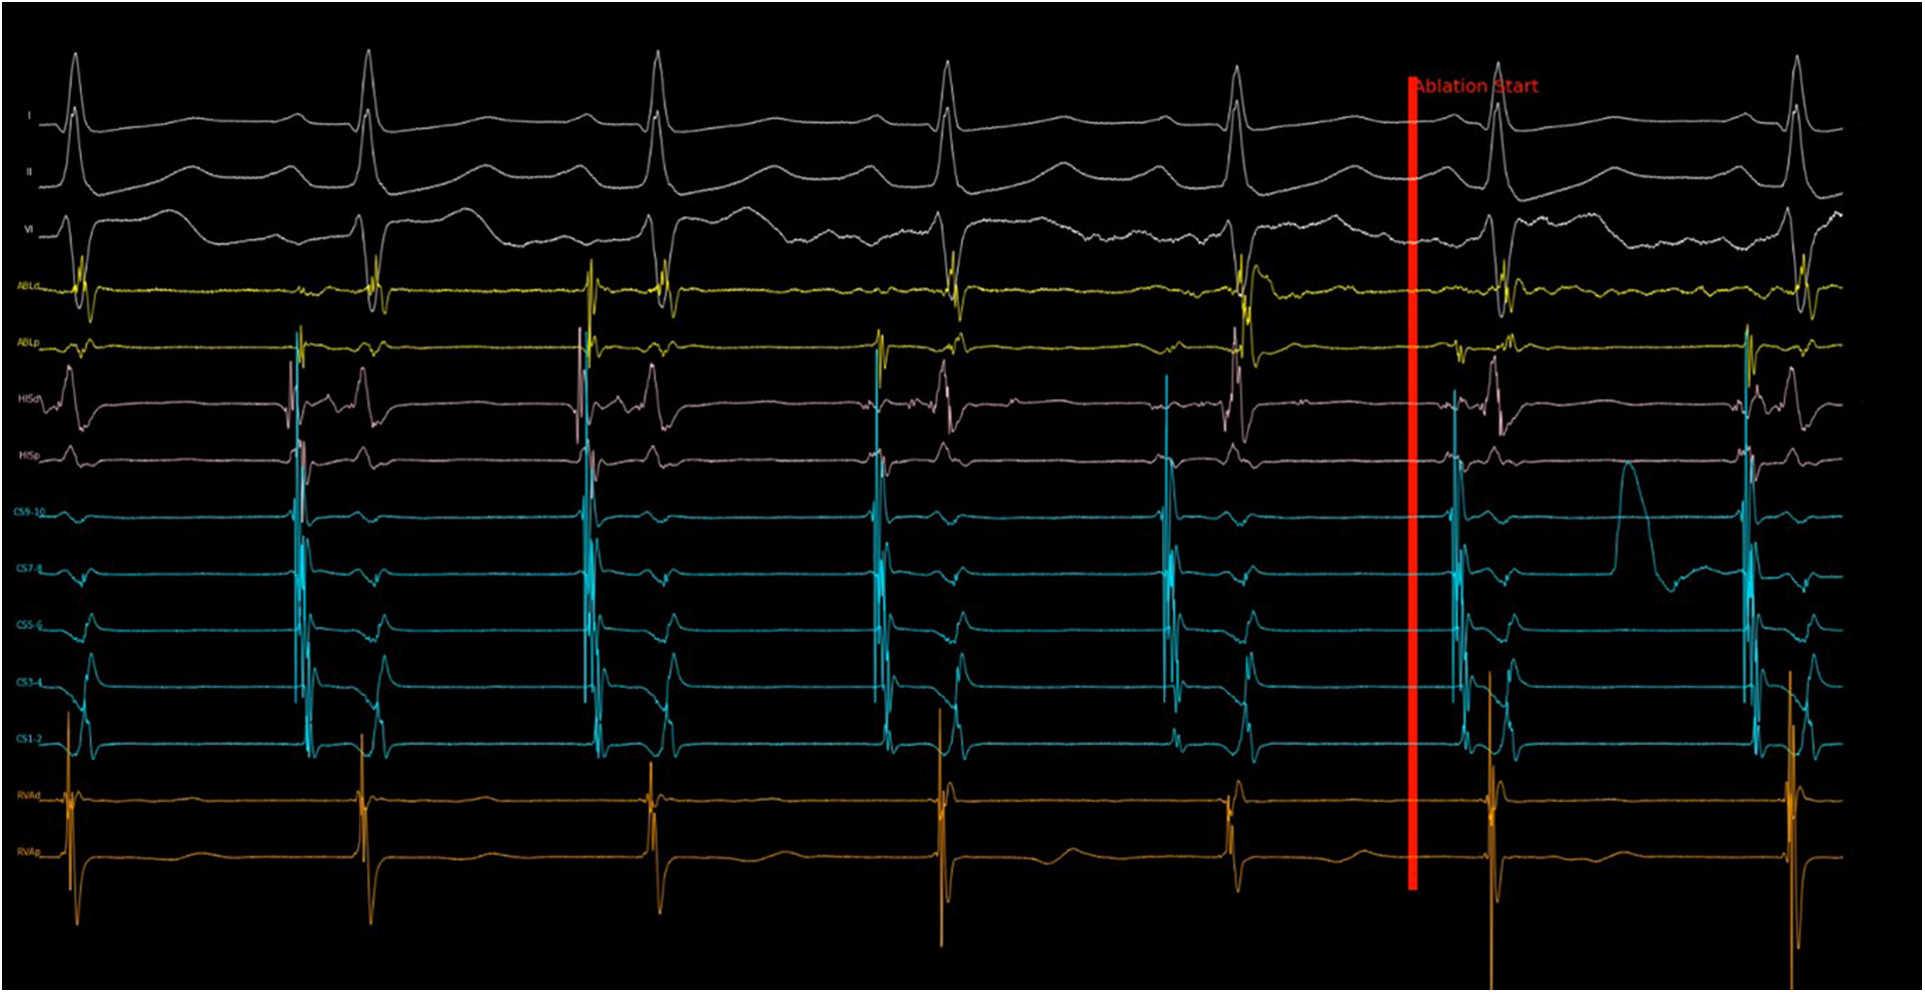

The exported EGM data was used to plot the 14 EGM channels and rendered into a video with a frame refresh rate of 100 Hz. Efforts were made to resemble real-time ablation as much as possible. The run time was displayed at the bottom left corner of the video. Because the same set of EGM data was used to feed into the final program, the time was synchronized between the video and the program. The video was shown to three independent electrophysiologists, who had no knowledge of program design. All three electrophysiologists were experienced in slow pathway modification procedures. Operator 1 and 2 each performed more than 100 procedures, and operator 3 performed more than 50 procedures. Although this simulation was designed to be intuitive, they each received training with videos generated from the training sets before analyzing the validation sets. They were instructed to step on a foot pedal before ablation started. A red line would be displayed at the start of ablation, and the operators would monitor the electrogram. If they recognized any high-risk features that prompted them to stop the ablation, they would release their foot from the pedal immediately. This action was registered by the computer as a command to pause the video. The ablation stop time at the bottom left corner would then be recorded. With this protocol, the human ablation-stop time could be determined with a precision down to 10 ms. Figure 1 and Supplementary Video S1 illustrate this process.

Figure 1. Demonstration of video simulation and calculation of AI lead time. 201 ablation runs in the validation set were rendered into ablation simulation videos at a frame rate of 100 Hz and played to three individual electrophysiologists. A foot pedal was used to control the video. Stepping down on the pedal would begin playing the video and releasing the pedal would stop the video. Upon pedal release, the time at the left lower corner would be recorded as the ablation stop time. This was compared with the ablation stop time determined by the program to calculate the AI Lead Time. A sample of the ablation simulation video can be found in supplementary material.